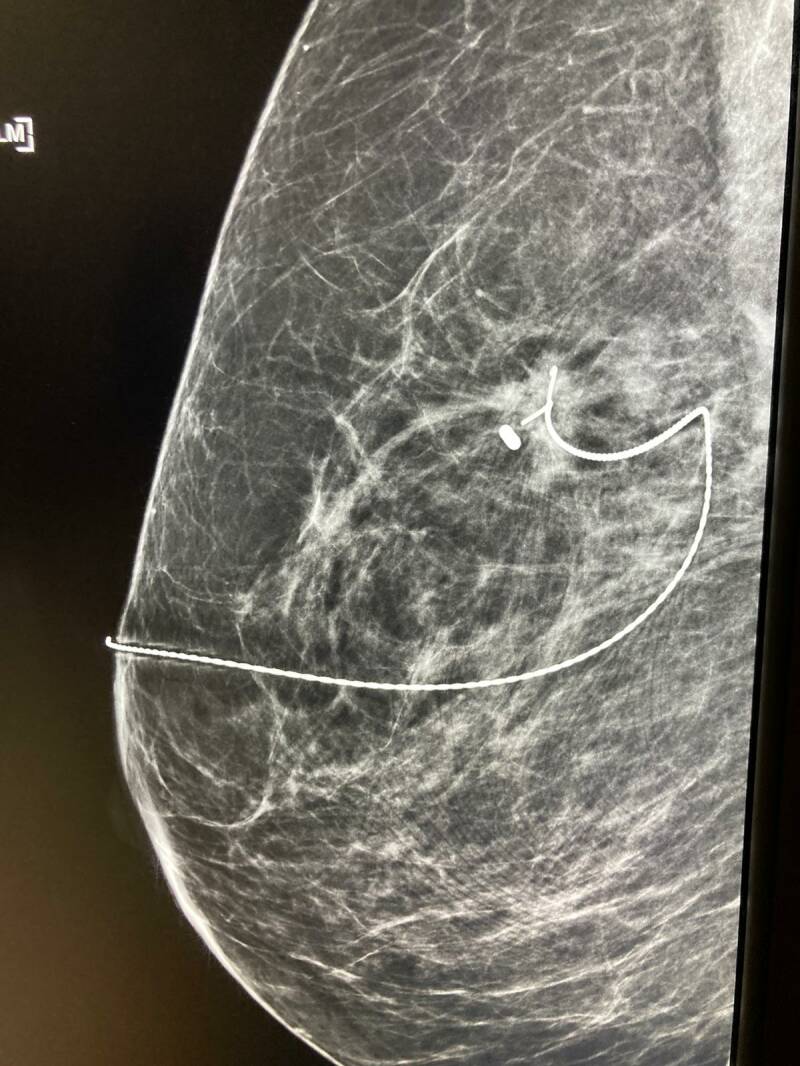

De dag begon met het aanbrengen van de tweede marker: de draad.

Dat ging niet helemaal lekker en moest opnieuw, maar zat volgens de deskundigen perfect op z'n plek. De foto's zijn gemaakt met de mammografie: Arvid " zag er niet heeel charmant uit, zo tussen de tosti-ijzers"

Op mijn borst met dikke stift de plek van de kanker en de diepte:2,5 cm.

Vervolgens pleisters om het uiteinde van de draad vast te pakken en om te voorkomen dat er stift op de mammografie-machine kwam. Owhja, en een mitella om mijn arm stil te houden en te voorkomen dat ik de draad zou verplaatsen met een beweging

Hier een foto van de mammografie waar de marker duidelijk zichtbaar is. De kanker zit er rechts naast.